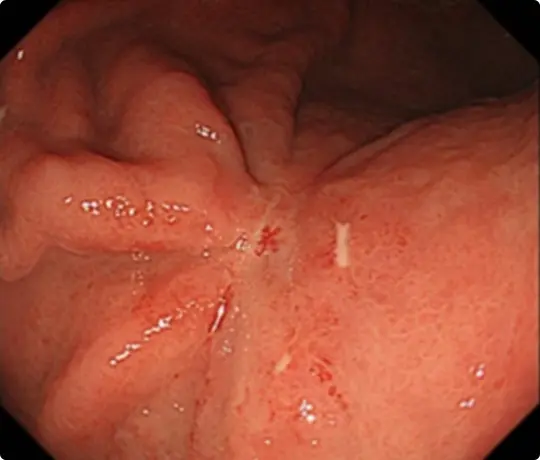

胃潰瘍瘢痕によるひだの集中像を認めます。

高度な線維化のため、難易度が高いと予想されます。

青い色素をかけて、がんの範囲を診断した後、電気メスで回りにマークを付けています。

粘膜の下に液体を注入した後、マークの外側の粘膜を電気メスで切開します。

粘膜の下の組織(粘膜下層)を電気メスで剥がしているところです。胃潰瘍の瘢痕による線維化があり、剥がせるスペースが限られています。筋層と粘膜下層の境界が分かりにくいため、慎重に剥離を進めます。

穿孔(壁に穴があくこと)などの問題なく、病変を切除しました。切除後は潰瘍が出来ますが、1~2ヵ月で治ります。